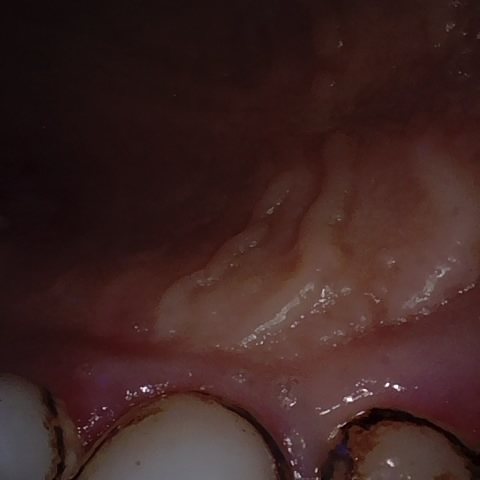

NHD30668

Annotated as "Good"